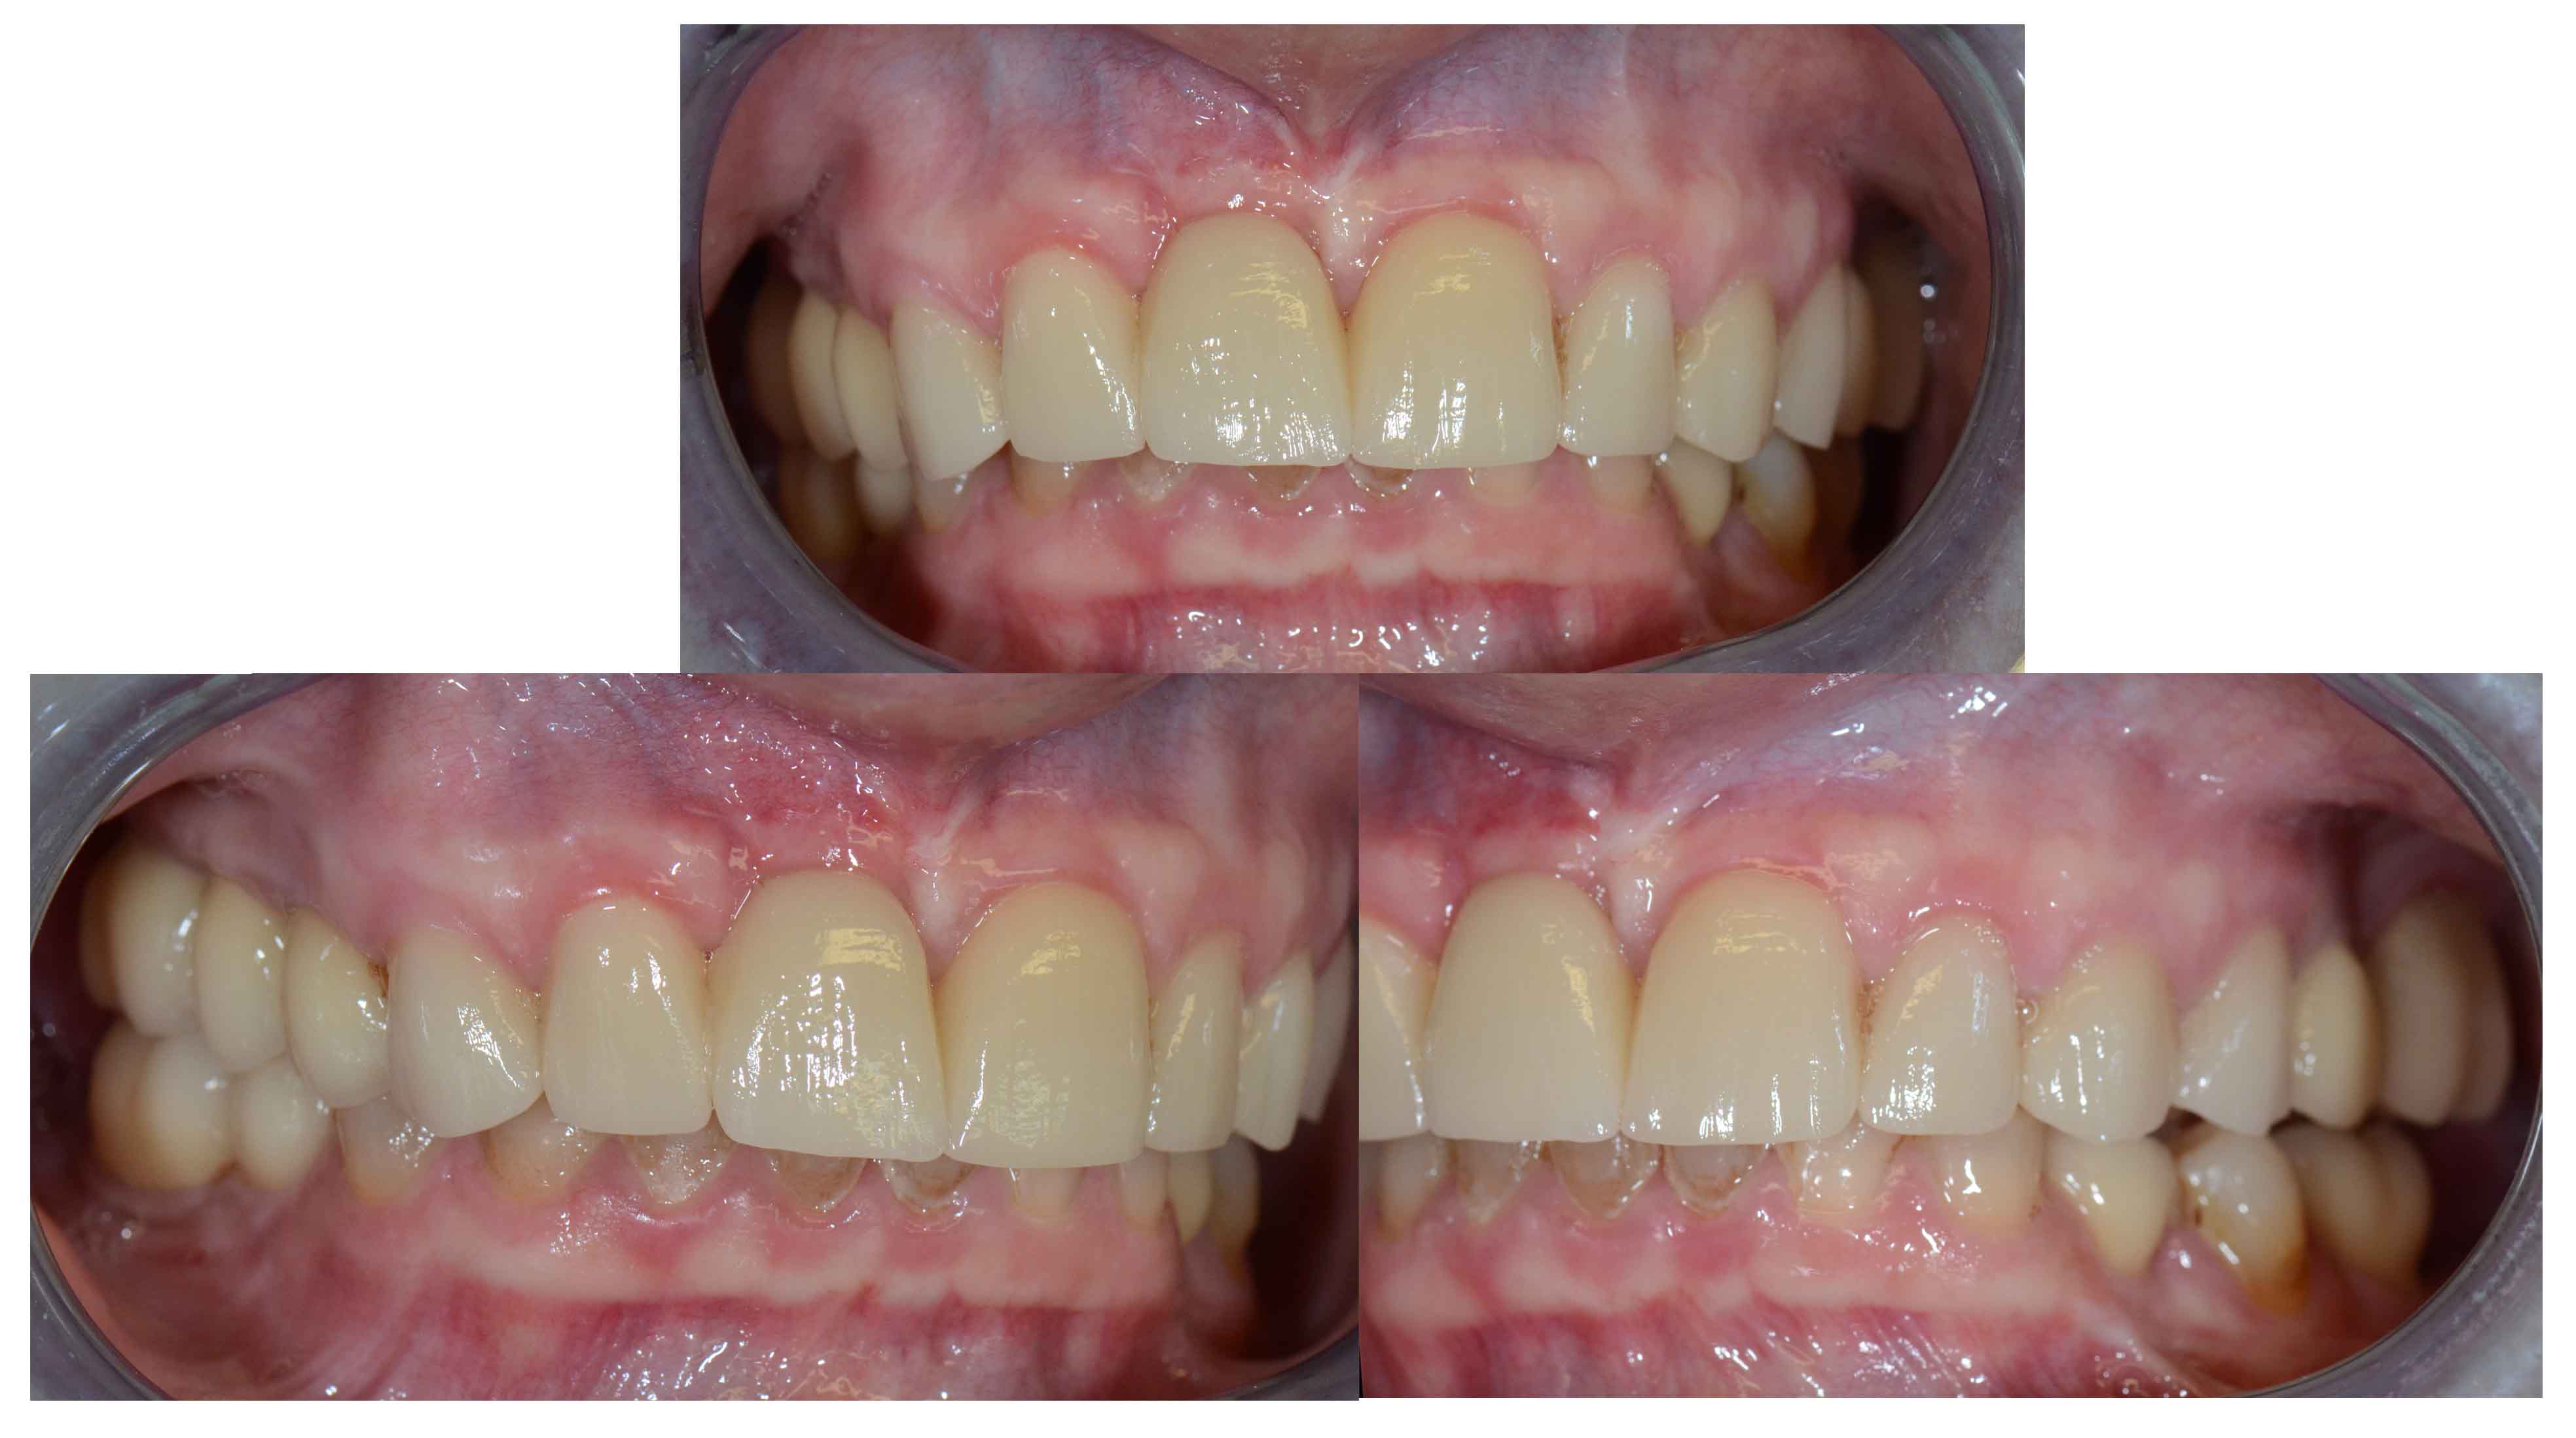

Alterações de Cor por Tetraciclinas

Reabilitação Estética com Coroas e Facetas Cerâmicas.

Problema Principal

Alterações de cor devido a utilização de Tetraciclinas em criança. Vários tratamentos feitos ao longa da vida para disfarçar o problema sem resultados satisfatórios.

Tratamento

Opção por recobrimento dentário com coroas nos dentes mais destruidos e de facetas naqueles menos atingidos evitando desgastes muito agressivos.